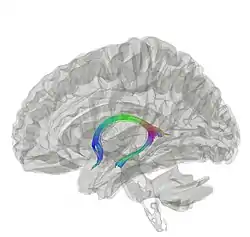

Diagram of the fornix. Right=anterior | |

Tractography showing fornix | |

The fornix (from Latin: fornix, lit. 'arch'; pl.: fornices) is a C-shaped bundle of nerve fibers in the brain that acts as the major output tract of the hippocampus. The fornix also carries some afferent fibers to the hippocampus from structures in the diencephalon and basal forebrain. The fornix is part of the limbic system. While its exact function and importance in the physiology of the brain are still not entirely clear, it has been demonstrated in humans that surgical transection—the cutting of the fornix along its body—can cause memory loss. There is some debate over what type of memory is affected by this damage, but it has been found to most closely correlate with recall memory rather than recognition memory. This means that damage to the fornix can cause difficulty in recalling long-term information such as details of past events, but it has little effect on the ability to recognize objects or familiar situations.

Structure

The fibers begin in the hippocampus on each side of the brain as fimbriae; the separate left and right sides are each called the crus of the fornix (plural crura). The bundles of fibers come together in the midline of the brain, forming the body of the fornix. The lower edge of the septum pellucidum (the membrane that separates the lateral ventricles) is attached to the upper face of the fornix body.

The body of the fornix travels anteriorly and divides again near the anterior commissure. The left and right parts separate, but there is also an anterior/posterior divergence.

- The posterior fibers (called the postcommissural fornix) of each side continue through the hypothalamus to the mammillary bodies; then to the anterior nuclei of thalamus.

- The anterior fibers (precommissural fornix) end at the septal nuclei of the basal forebrain and nucleus accumbens of each half of the brain.